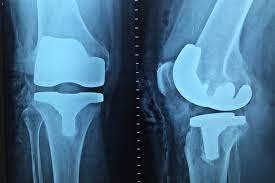

V krajním případě, kdy nepomohly léky nebo způsobují těžké vedlejší účinky, se přistupuje k chirurgické léčbě. Například nefunkční kloub se nahradí umělým.

Stejně jako u artritidy se užívají léky na úlevu od bolesti. Silné bolesti se zahání injekcemi kortikosteroidů. V počátečních stádiích je možné udělat ošetření kloubních struktur. Dále je možné podstoupit operaci na úpravu osy kloubu, které má za úkol minimalizovat jednostranné přetížení kloubů. Těžké postižení opět vede ke kloubní náhradě.